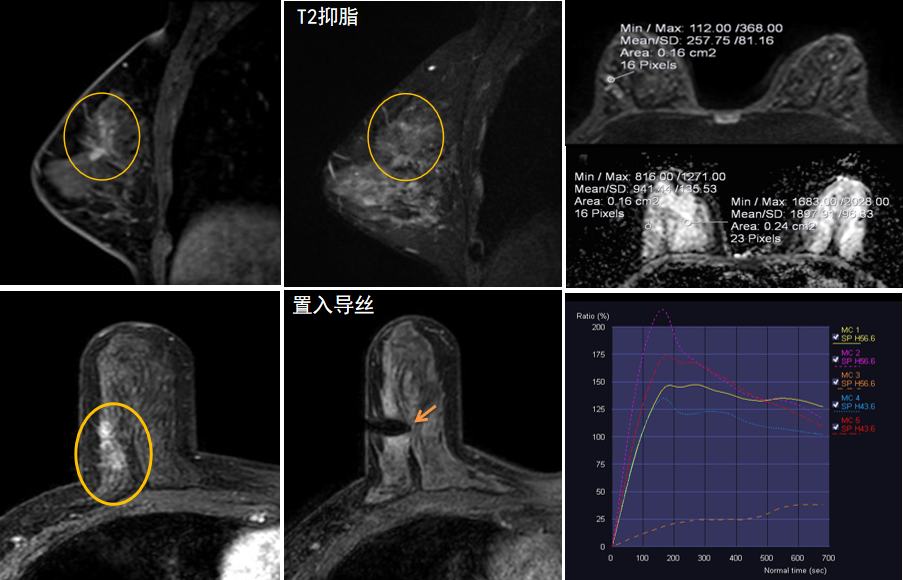

今年45歲的某女士,兩個(gè)月前行超聲檢查發(fā)現(xiàn)右乳結(jié)節(jié),乳腺X線攝影檢查提示右乳外上象限局部腺體結(jié)構(gòu)扭曲并簇狀無(wú)定形鈣化,為了進(jìn)一步評(píng)估病變性質(zhì)并確定范圍進(jìn)行了乳腺M(fèi)R平掃 DWI 增強(qiáng)的檢查,經(jīng)MR評(píng)估發(fā)現(xiàn)右乳病變范圍較廣,評(píng)估為BI-RADS 4類(lèi)可疑病變,需要取得病理學(xué)結(jié)果。

只能借助影像學(xué)引導(dǎo),但超聲僅顯示了病變中的小結(jié)節(jié),X線攝影(鉬靶)顯示的病變邊界比較模糊,要想做到精準(zhǔn)完整切除必須借助MR的引導(dǎo),而這一技術(shù)對(duì)軟硬件平臺(tái)及人員技術(shù)都有很高的要求,因此,多年來(lái)一直是我國(guó)乳腺病變?cè)\療的盲區(qū),經(jīng)常是MR發(fā)現(xiàn)可疑病變但卻無(wú)法處理。目前全國(guó)僅有少數(shù)幾家醫(yī)院開(kāi)展了這方面的部分工作。

西安國(guó)際醫(yī)學(xué)中心醫(yī)院影像診療中心陳寶瑩主任團(tuán)隊(duì)有著十余年影像引導(dǎo)下乳腺介入診療的經(jīng)驗(yàn),借助醫(yī)院高精尖的MR平臺(tái),成為西北首個(gè)全面展開(kāi)MR引導(dǎo)下各項(xiàng)乳腺介入診療技術(shù)的團(tuán)隊(duì),能夠?qū)Τ暭叭橄賆線無(wú)法顯示或顯示不清的病變進(jìn)行MR引導(dǎo)下的導(dǎo)絲定位、穿刺活檢及真空輔助旋切。

陳寶瑩主任及其帶領(lǐng)的MR介入診療小組詳細(xì)詢問(wèn)了病情,分析了患者資料,并與患者和臨床醫(yī)生進(jìn)行了充分溝通,確定于手術(shù)前為患者實(shí)施MR引導(dǎo)下的病變穿刺導(dǎo)絲定位和體表范圍確定。手術(shù)前陳寶瑩主任帶領(lǐng)聶品醫(yī)師、馬小偉技師、韓愛(ài)萍護(hù)士長(zhǎng)等MR介入診療小組成員,借助MR高清的圖像顯示和定位系統(tǒng),確定病變范圍,精準(zhǔn)穿刺置入定位導(dǎo)絲,并準(zhǔn)確標(biāo)記出病變體表范圍,整個(gè)過(guò)程患者無(wú)任何不適。在定位導(dǎo)絲和體表范圍標(biāo)記的輔助下,甲乳外科劉曉敏主任精準(zhǔn)切除了病變,解除了患者的后顧之憂。

國(guó)內(nèi)外指南均建議40歲以上的女性每年行一次雙乳X線攝影(鉬靶)檢查,以篩查乳腺癌。對(duì)于乳腺癌高危人群40歲以前即建議開(kāi)始乳腺癌篩查,除了進(jìn)行乳腺X線攝影(鉬靶)篩查外需要補(bǔ)充MR檢查,MR檢查敏感性最高,能夠發(fā)現(xiàn)大量X線攝影和超聲檢查陰性的可疑病變,基于多模態(tài)、多參數(shù)的結(jié)構(gòu)和功能成像的基礎(chǔ)上,MR能夠精準(zhǔn)顯示病變位置、范圍以及病變內(nèi)的活性區(qū)域,MR引導(dǎo)下的介入診療不但解決了僅在MR顯示的病變的處置難題,而且能夠精準(zhǔn)定位活性區(qū)域,保證了定位、活檢及旋切的準(zhǔn)確性。